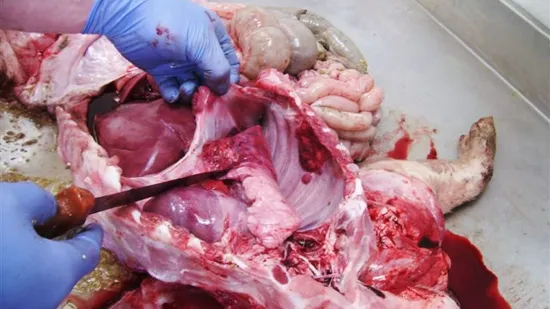

Episode de morts subites, manque d'appétit, forte fièvre et toux chez les porcs entre 10 semaines de vie et l'abattage. Une pneumonie nécrosante et de la pleurésie sont détectées dans le lobe diaphagmatique. Quelle en est la cause ?